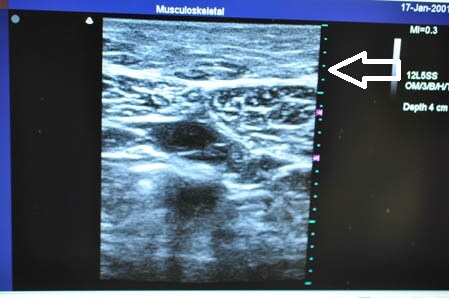

上の画像の部分の皮下脂肪層を

つまんでみることにしましょう。

↓ ↓ ↓